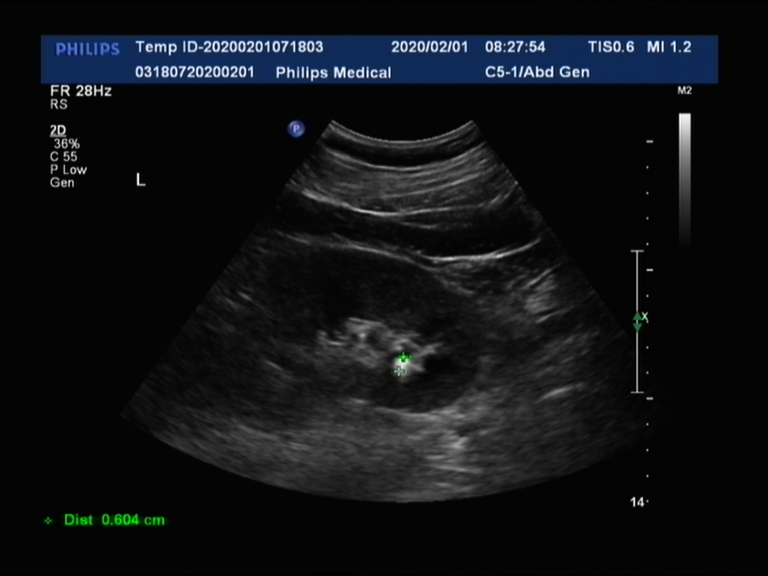

白色亮点就是肾结石

1. 结石直径0.5~1cm,其中以0.6cm为适宜;

一般肾结石是不引起疼痛的,引起疼痛的往往是输尿管结石